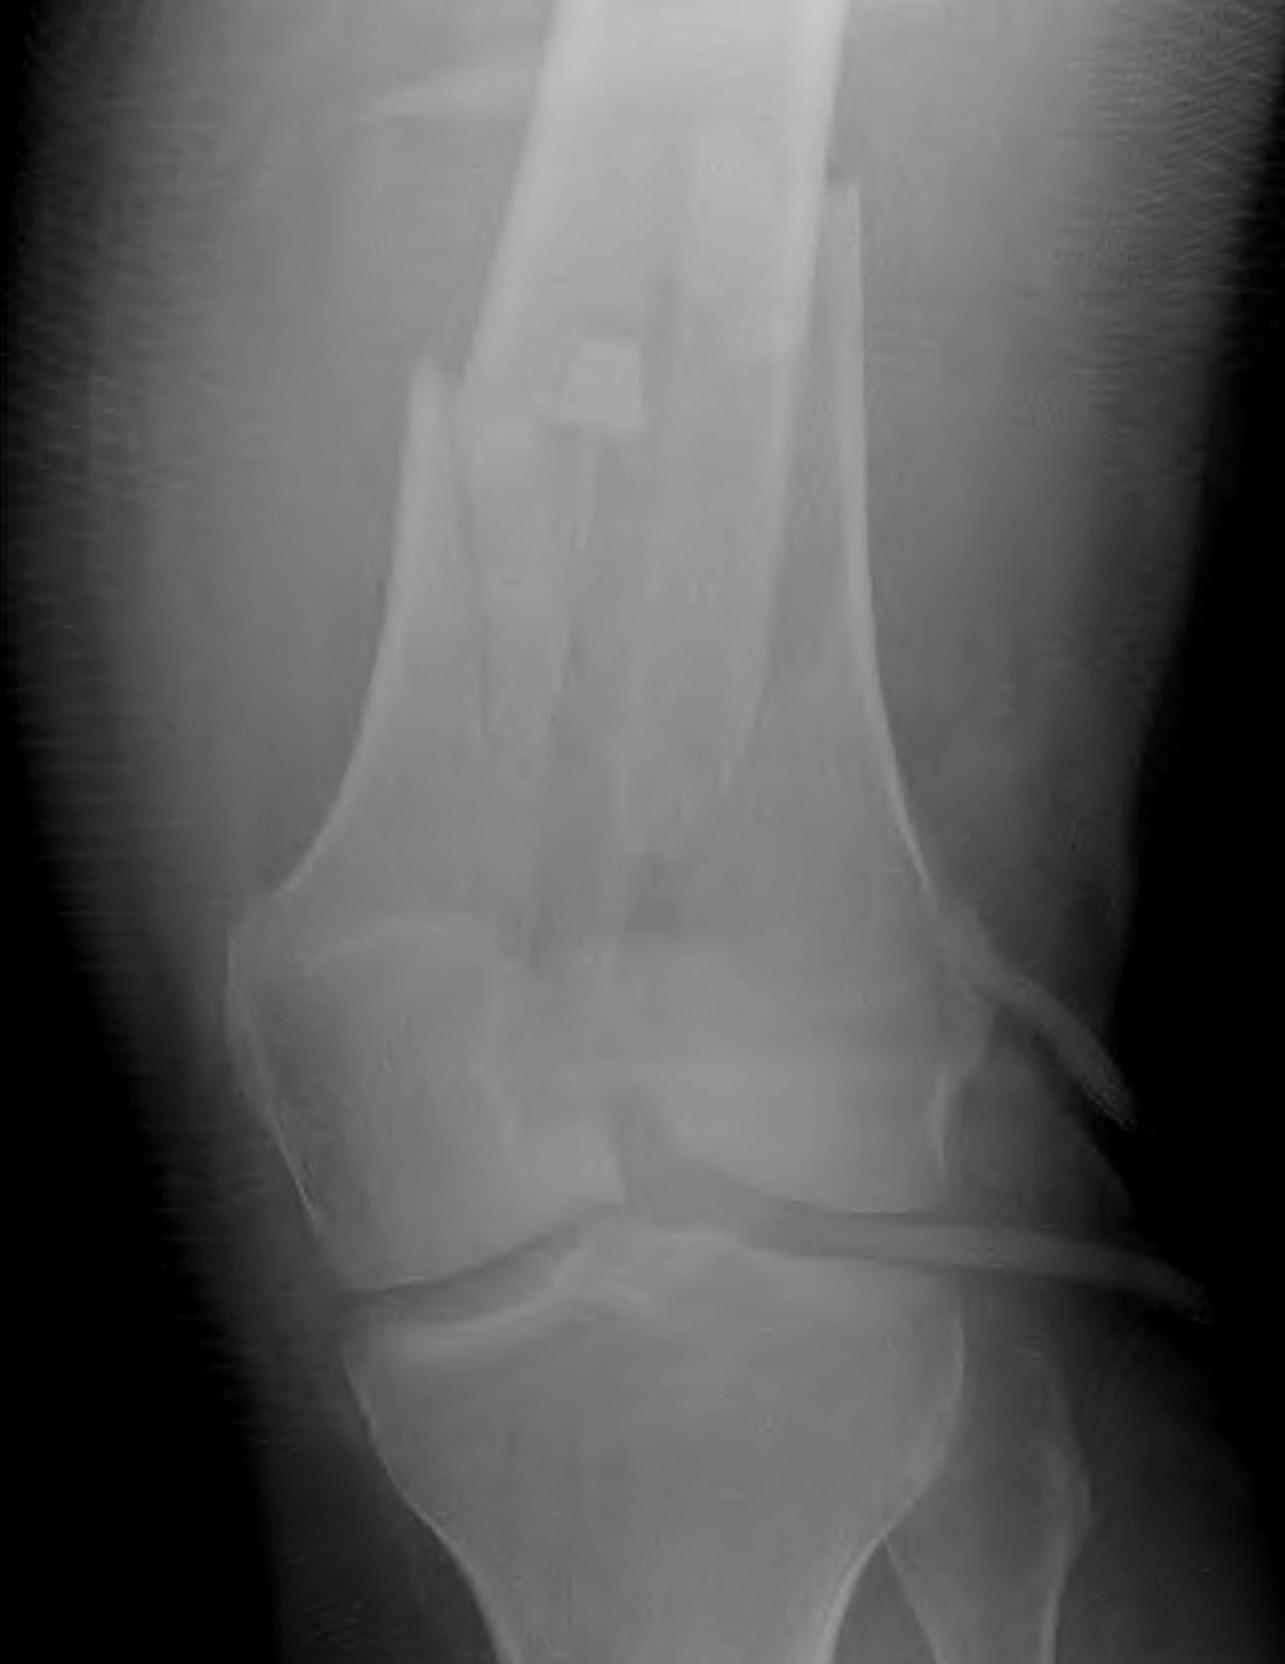

AO Type B1 & B2: Partial articular

![]()

Definition

Medial or lateral sagittal split

Technique

ORIF

- medial or lateral approach based on fracture location

- reduce articular split and fix with screws

- medial or lateral buttress plate

Lateral split fracture distal femur